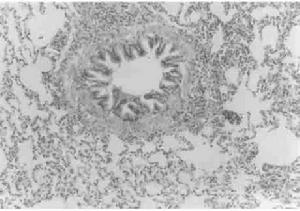

病理

1、結核、外傷等引起的疤痕病變。

2、氣管切開後引起的疤痕性氣管支氣管狹窄。

3、惡性腫瘤引起的氣管支氣管狹窄。